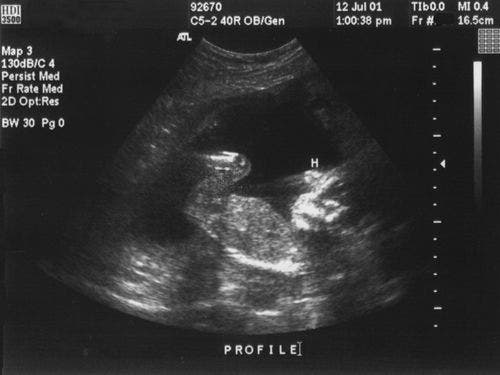

Le déphasage, ou phasage, est un moyen de contrôler ces interactions en phasant dans le temps des fronts d’ondes de deux ou plusieurs sources. Il peut être utilisé pour infléchir, orienter ou concentrer l’énergie d’un front d’onde. Dans les années 1960, les chercheurs ont commencé à concevoir des systèmes à ultrasons multiéléments qui utilisaient des sondes à multiples points sources qui généraient des faisceaux acoustiques basés sur ces modèles d’interférence contrôlée. Au début des années 1970, les premiers systèmes multiéléments commerciaux de diagnostic médical généraient des faisceaux dirigés qui créaient des images en coupe transversale du corps humain.

Au départ, l’utilisation des systèmes à ultrasons multiéléments a été confinée principalement au domaine médical, surtout parce que la composition et la structure prévisibles du corps humain rendent la conception des appareils et l’interprétation des images relativement faciles. Les applications industrielles, par contre, représentent un défi beaucoup plus grand en raison des propriétés acoustiques très variables des métaux, des composites, des céramiques, des plastiques et de la fibre de verre, ainsi que de l’énorme variété d’épaisseurs et de formes rencontrées dans le cadre des inspections industrielles. Le premier système multiélément industriel, commercialisé durant les années 1980, était de très grande taille et nécessitait un transfert des données vers un ordinateur pour le traitement et la présentation des images. Ces systèmes ont été le plus souvent utilisés pour l’inspection des centrales électriques en fonctionnement. Cette technologie a surtout été développée dans l’industrie du nucléaire, où l’évaluation critique favorise beaucoup l’utilisation des technologies de pointe pour améliorer les probabilités de détection. D’autres applications ont également été développées pour l’inspection des grands arbres forgés et des composants des turbines basse pression.